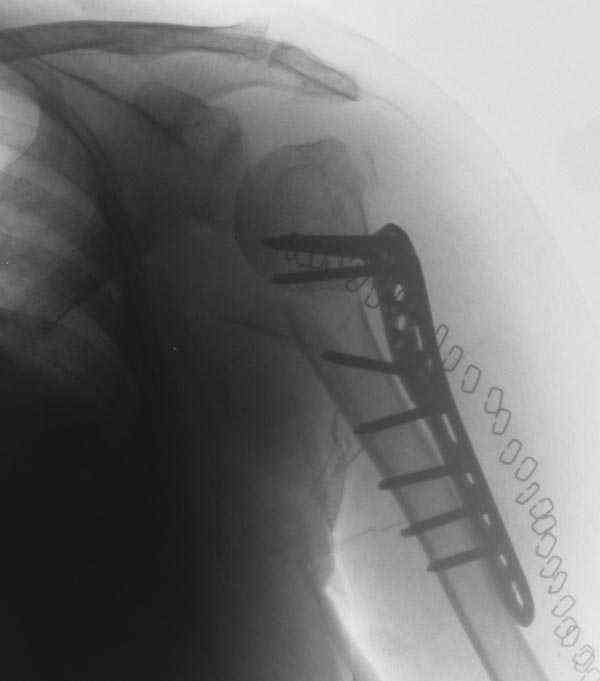

The reduction is not perfect. The patient is very small made, and it was difficult to bring the plate proximally without impingement in abduction.

Pain relief after surgery was early and sustained.